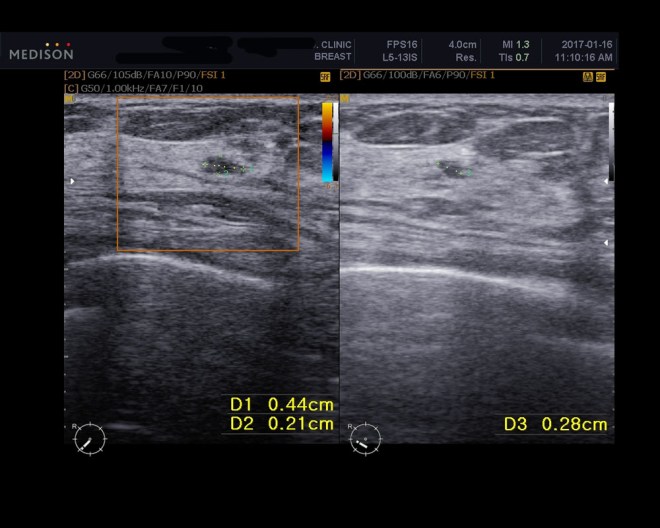

이 환자는 1년간 내 치료를 잘 따라 주었고 마음이 안정이 되어서 현재 사회생활도 하고 있다. 5월중에 초음파를 다시 비교하였다. 2017년 1월달에 추적검사를 하였고 다시금 5개월 뒤에 추적검사를 하였다.

1. 2017년 1월 16일 초음파 추적검사

우지연 1-3-1.JPG

우지연 1-5.jpg

이미 알려진 우측하부의 유방암으로 화학치료와 방사선 치료를 끝낸 상태

특별히 설명할 만한 잔여 종양이나 재발된 종양은 우측유방에 보이지 않는다. 그러나 조그마한 미세석회화 부분이 6방향에 보인다.

작은 3mmx4mm 크기의 저밀도로 보이는 부분이 7시 방향에 보이는데 이는 위성종양인지 의심이 된다.

좌측유방과 우측의 겨드랑이 부분에 특별한 것이 보이지 않는다.

2017년 5월 26일 초음파 추적검사

우지연 1-1.JPG

우지연 1-6.jpg

이미 판명된 우측 아래쪽 바깥 사면의 유방암으로 화학치료와 방사선을 받은 상태.

특별히 설명할 만한 잔여의 종양이나, 재발된 종양은 보이지 않는다. 조그마한 미세 석회화와 비정형의 낮은 조영증강의 부분이 보이는데 이는 아마도 방사선 치료 후의 변화로 보인다.

조그마한 정형을 가지지 않는 저밀도의 부분이 오른쪽 7시 방향에 여전히 보이는데 이는 이전 초음파 상에서 보였던 것과 변화가 없다. 아마도 양성의 부분으로 보인다.

양쪽 겨드랑이와 왼쪽 유방에는 특별한 것이 없다. 6개월 뒤에 다시 추적할 것을 권유한다.